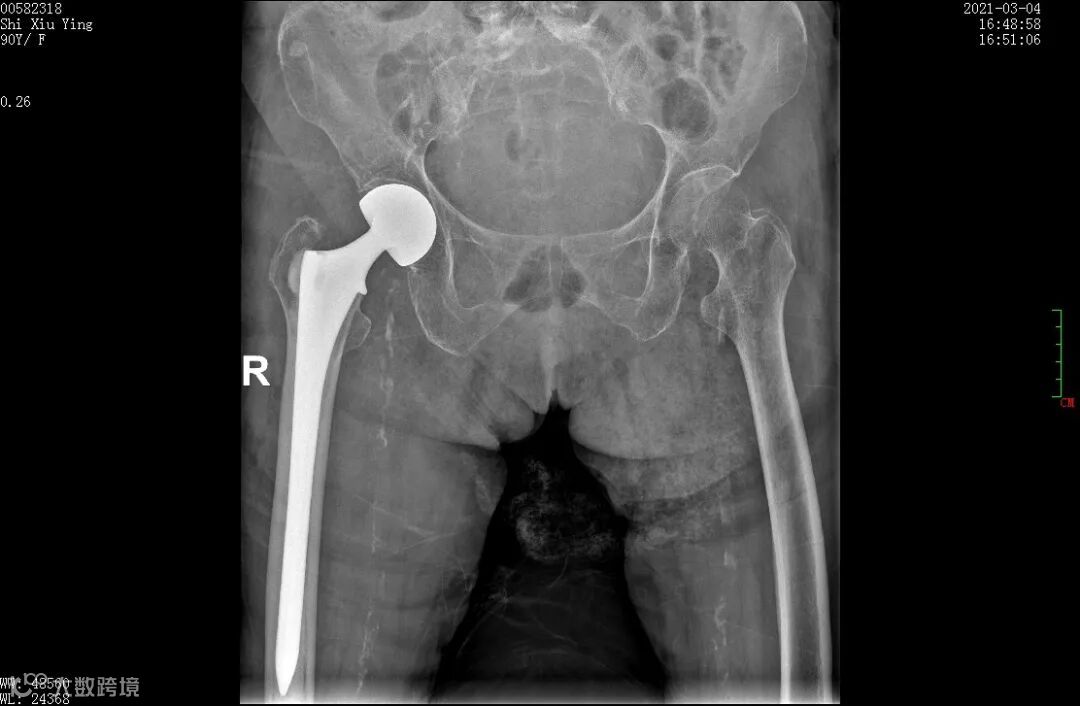

3月2日上午,罗世兴主刀为石奶奶进行“右侧人工关节置换”手术,采取椎管内麻醉,手术过程顺利,仅用时30分钟已完成大部分手术步骤,但手术过程中出现一点小插曲。注入骨水泥前,邓喆提前对石奶奶升压、给氧,但患者的血压、血压氧饱合度仍出乎意外突然往下掉,收缩压从120mmHg一下子掉到70mmHg,血氧饱和度从100%掉到70%”,罗世兴回忆道。

3月4日下午,术后的第三天,石奶奶恢复良好,已经能够下地行走,近期即可出院。